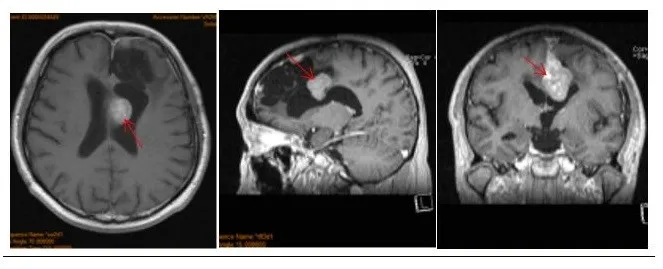

术前情况:48岁的赵先生因突发癫痫就医,家人带其MRI检查后发现大脑左额镰旁有肿瘤占位,立即在国内某医院进行部分切除,病理结果是“脑膜瘤”。由于赵先生肿瘤生长在特别重要的神经、血管旁,为保留神经、血管功能,手术全切难度大,较易损伤周边重要组织,所以只实施了部分切除。

然而仅在部分切除手术的二年,赵先生就在复查检查种发现了脑膜瘤复发的情况,手术风险依旧存在,医生建议赵先生进行伽马刀治疗。3年伽马刀治疗非但没有如预期的控制肿瘤生长的效果,反而让赵先生的脑膜瘤继续恶化,MRI影像显示大脑镰前段基本均受累,并有大脑镰右侧肿瘤生长,矢状窦被累及,左侧额部凸面硬脑膜多处肿瘤生长。

治疗过程:看完赵先生的影像资料,巴特朗菲教授指出,能否完整切除脑膜瘤是预防脑膜瘤复发的关键因素,这也决定了患者术后能否有更高的生存率、更好的生活质量。虽然二次手术风险大,凭借其多年的经验可把当前的脑膜瘤及残余全部清除。

术中情况:在术中iMRI、术中神经导航等国内少有的高科技复杂仪器辅助下,巴特朗菲教授为赵先生实施了手术,大脑镰旁及矢状窦旁的肿瘤被完全切除,受累颅骨的内板以磨钻磨除后复位。手术实现脑膜瘤Simpson 1级切除。

术后情况:术后ICU观察一天,术后二天下床进行康复锻炼。神经功能无任何异常,术后13天步行出院。距离赵先生做手术已有5年多了,赵先生的女儿每年都会陪父亲定期去坐核磁检查,而MRI复查结果显示,脑膜瘤并没有复发,在国内做了的康复治疗后,除了定期复查,赵先生现在已跟正常人一样生活。